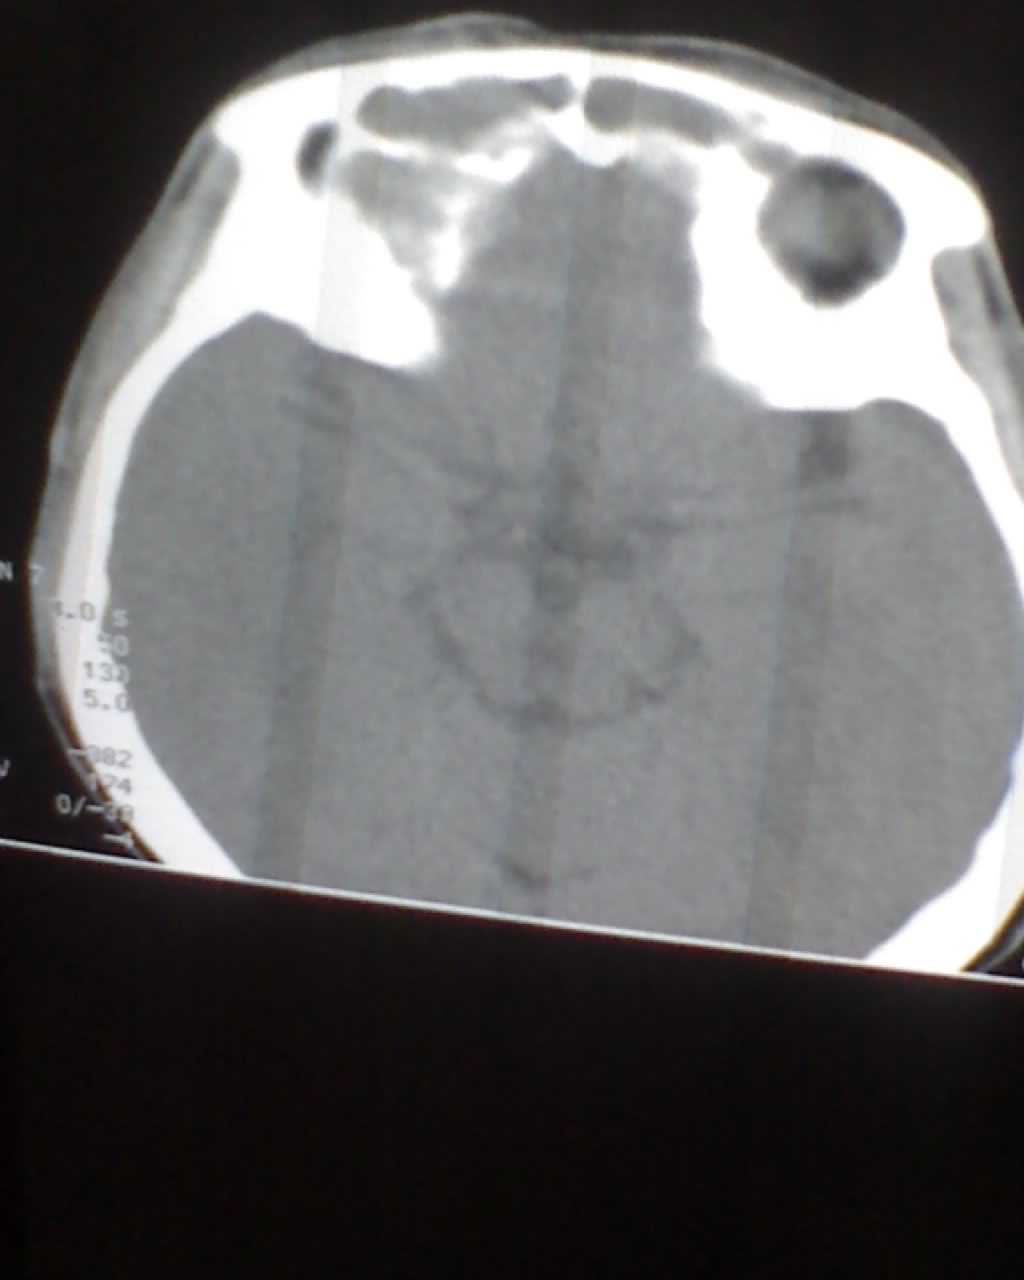

女,45岁,右眼突出,视力模糊来诊。

双侧筛窦可见软组织影充填,筛板破坏,肿块突向双侧眼眶内,以右侧为明显,右侧眼球向前外推压,右视神经稍外移。

考虑良性病变,内翻乳头状瘤可能性大,不除外息肉等。支持!(病灶明显起源于鼻窦,呈膨胀性生长,周边骨质吸收 破坏)。

双侧额窦,筛窦可见软组织影充填,筛板破坏,肿块突向双侧眼眶内,以右侧为明显,右侧眼球向前外推压,右视神经稍外移。

考虑良性病变,黏液囊肿可能性大,不除外内翻乳头状瘤等,建议强化.前者不增强.